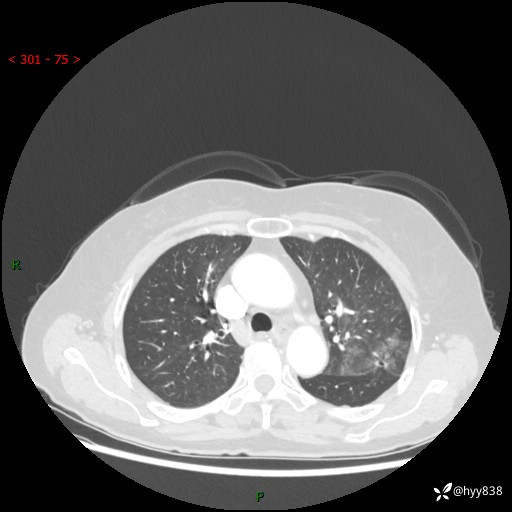

老年女性,偶然发现肺结节10天。结节不大,空洞不小,还牵拉胸膜---结果公布~

年龄:68岁

主诉:体检发现肺结节10余天

现病史:患者10余天前因“左侧鼻塞伴鼻腔异味2月”就诊于我院耳鼻喉科,查胸部CT示:左上肺结节影,建议复查。患者偶有咳嗽、咳痰,多咳白痰,无畏寒、发热,无胸痛、呼吸困难等,现为进一步明确肺结节性质,就诊于我科门诊。现以“孤立性肺结节”收住我科。 起病来,患者精神、食欲、睡眠尚可,体力、体重无明显变化。

胸部CT(2024.7.16)